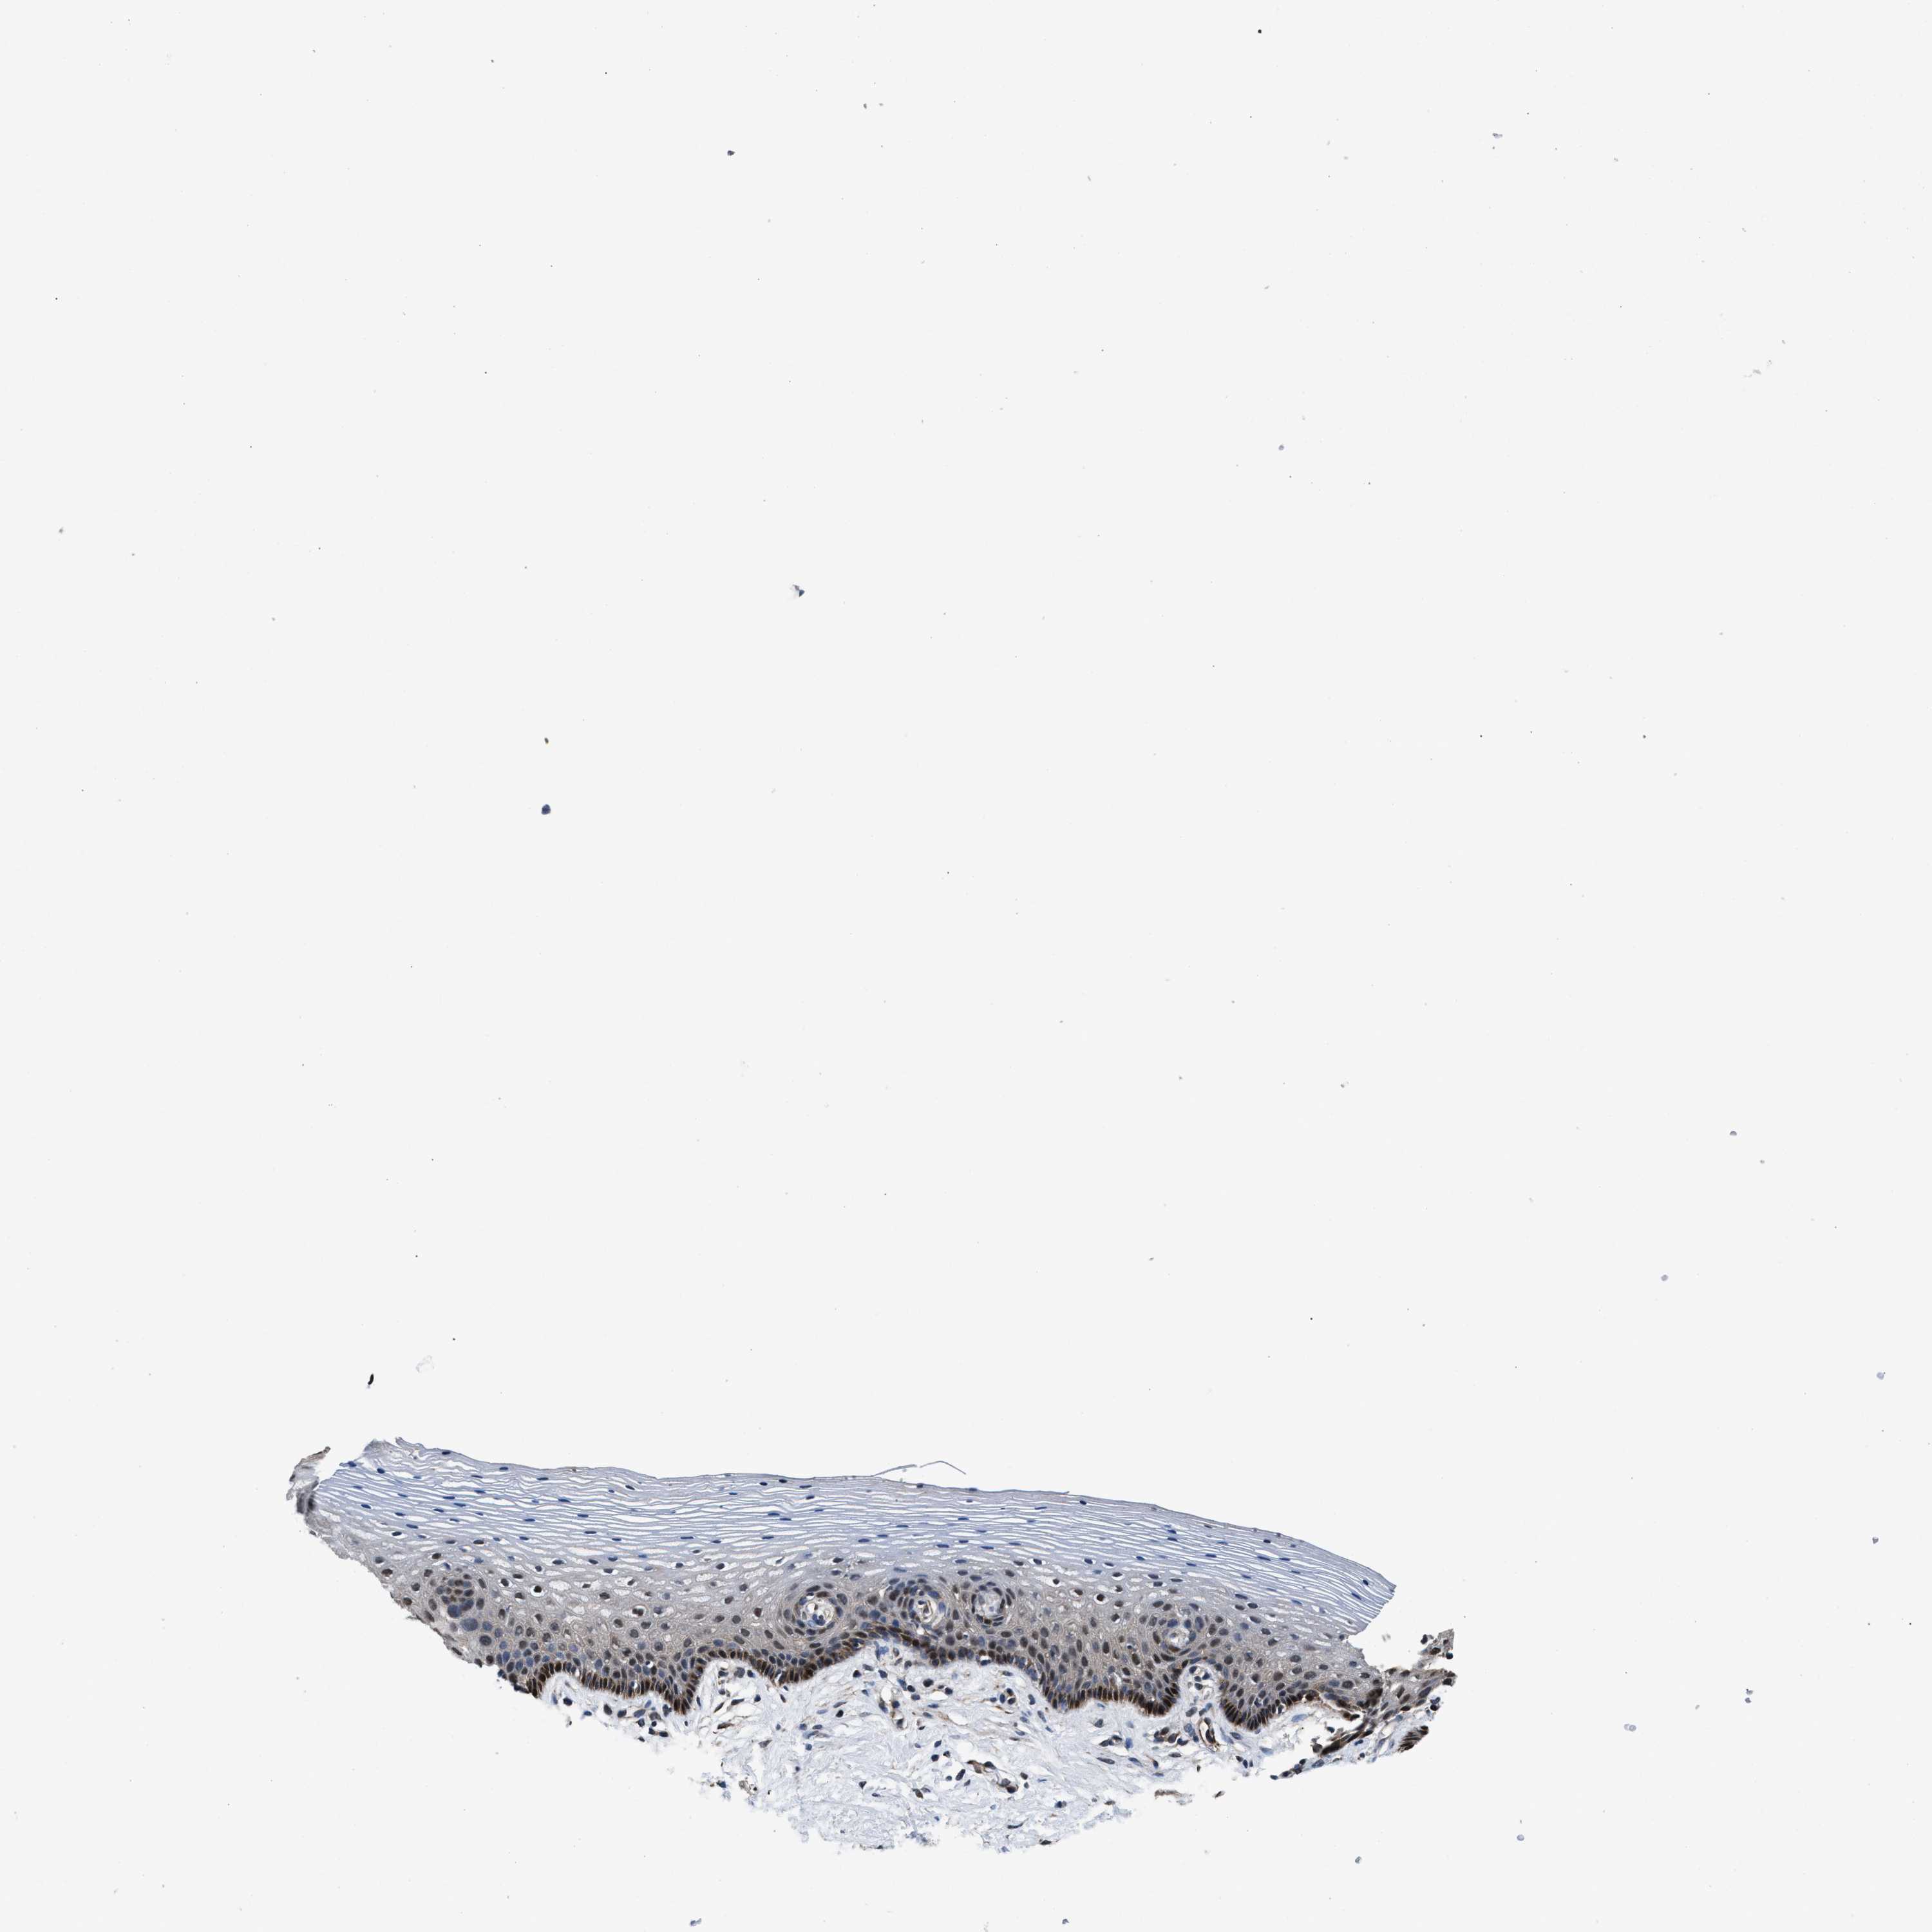

VAGINA - Antibody stainingi

Antibody staining in the annotated cell types in the current human tissue is reported as not detected, low, medium, or high, based on conventional immunohistochemistry profiling in selected tissues. This score is based on the combination of the staining intensity and fraction of stained cells.

Each image is clickable and will lead to virtual microscopy that enables deeper exploration of all samples and also displays staining intensity scores, fraction scores and subcellular localization as well as patient and tissue information for each sample.

Antibody HPA019232Antibody HPA021497Antibody HPA021768

Squamous epithelial cells LowNot detectedHigh